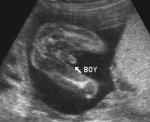

Kdyby ta fotka vypadala takhle nebo takhle, bylo by to jiné :)

Vypadá to jako kluk. Ale jiste to bude stejně až po porodu. :-D